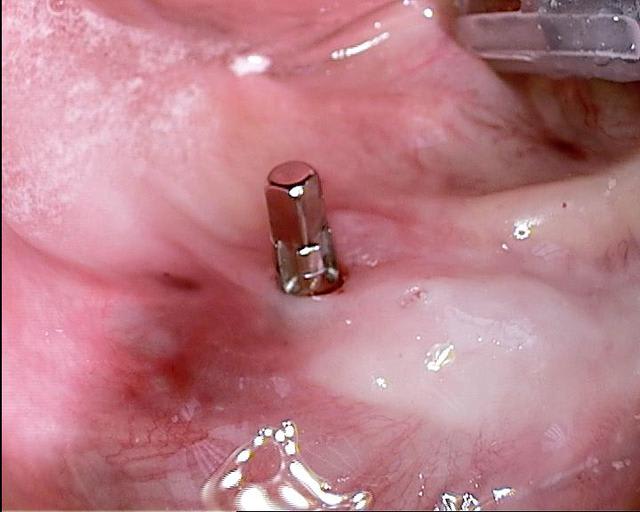

-pour la praticité le système que j utilise , seulement besoin de 5min pour poser l implant et cémenter le prepcap encore 5 min (tu peux le préparer comme une simple dent)

Pour compléter le cas du dr Nedjat, dont j'utilise depuis plus de trois ans techniques et implants voilà un traitement d'édentement complet (en cours) avec des monoblocs aux axes corrigés par des prep caps en titane ou zircone qui sont cémentés. La prothèse complète du patient a été transformée en provisoire de qualité car au programme mois prochain il y a le bas..Toutes les photos et radios ont été faites jour de la pose. sauf la pano avant les ext bien sur :)